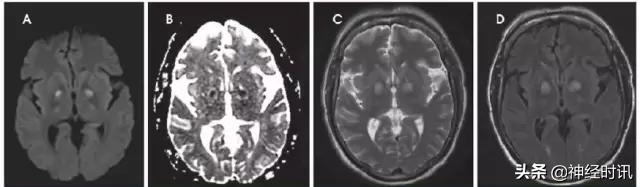

图7 一例31岁男性,有*洛因海**和*卡因可**滥用史,出现无脉性电活动心搏骤停。MRI显示双侧顶枕叶和额叶、双侧丘脑弥漫性弥散受限(A:DWI,B:ADC)、T2-FLAIR高信号(C:FLAIR),符合全脑缺氧性损伤。

缺血缺氧性脑病(HIE)是全脑缺氧的结果。最常见的原因是心脏骤停、呼吸衰竭和休克。严重的患者大脑皮质和深部灰质均受累(图7)。较轻的患者可以见到边缘带梗死类型。罕有纯白质型,这可能是全脑缺血诱发脱髓鞘表现。小脑通常不受累。